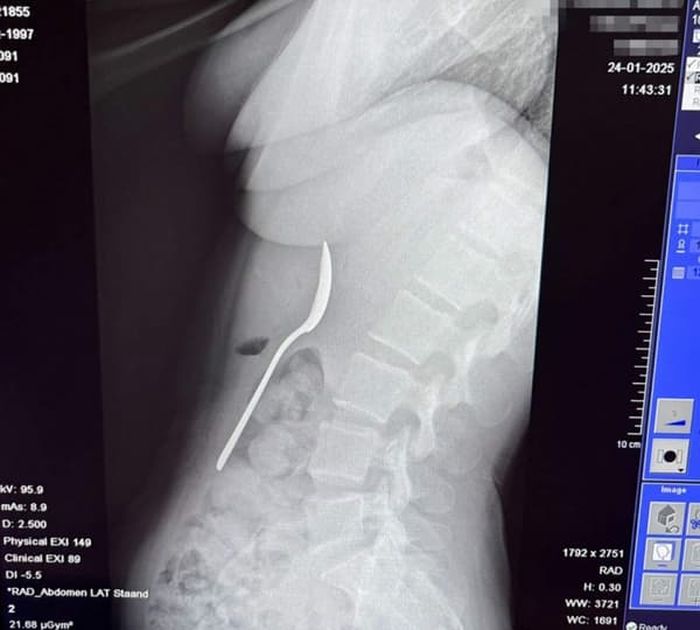

인터넷을 검색해본 레이미 씨는 상황이 매우 심각하다는 것을 깨닫고 급히 응급실로 향했습니다. 엑스레이를 찍어보니 정말로 기다란 숟가락이 그녀의 위장에 떡하니 자리 잡고 있었죠.

의사들은 숟가락이 너무 커서 자연적으로 배출될 수 없다고 진단했습니다. 이틀 동안 수술을 기다리는 내내 그녀는 갈비뼈 사이로 숟가락이 부딪히는 소름 돋는 느낌을 참아야 했습니다.